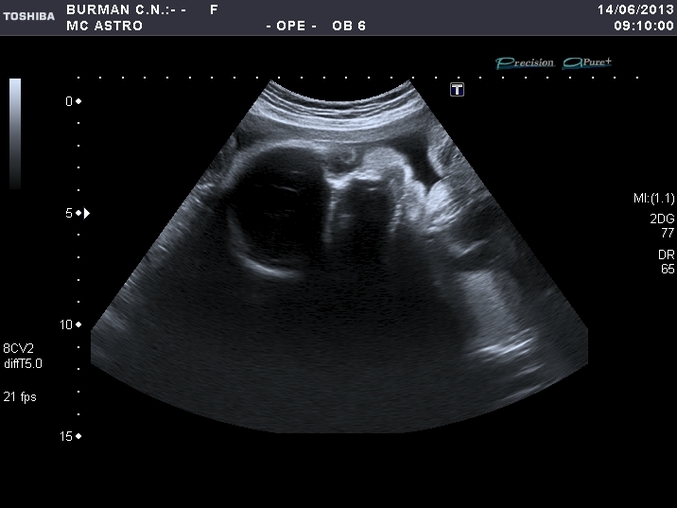

Посещение и назначения врачей (стоматологи, кардиологи и проч.)Такие солнечные планы были на сегодня, собирались нашего малыша смотреть на узи 4D. Оно у нас только появилось в городе, поэтому не смотря на срок, решили сходить.

Я была в шоке. В 4D ничего не показали, якобы вод мало и лежит ребенок неудачно. Но в итоге написали, что вод нормальное количество. КАК ТАК????? Видео записали в 2D. Потом оказалось, что размеры никакие не сохранились, вес вообще не померили. Короче, меня собирались отпустить ни с чем

В итоге по первому узи сейчас 31 неделя, по второму узи, почти 31 без нескольких дней, по этому узи 28((((((( Вес всего 1250. Рост даже не померили.

Радует одно, на экране я видела пухлощекого малыша, видела ручки, ножки, сердечко.